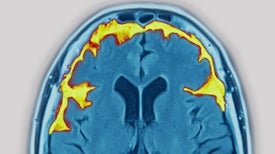

Understanding Frontotemporal Dementia, the Leading Cause of Dementia in People under Age 60

There is no cure for FTD, the disease that actor Bruce Willis was recently diagnosed with, but new research suggests some future therapies

The pathological buildup of a protein known as TDP-43 can lead to an Alzheimer’s-like disorder